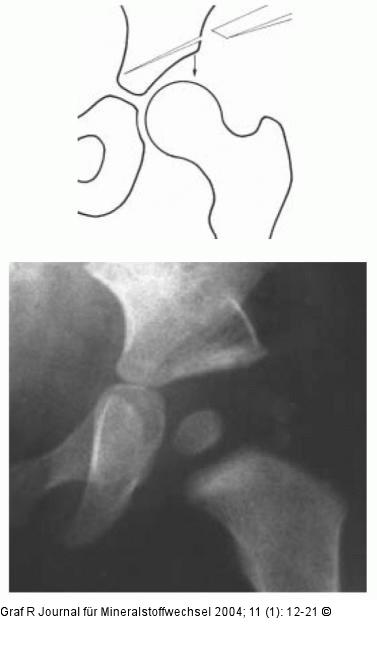

Abbildung 11: Hüftgelenk Prinzip der Acetabuloplastik. Schräges Einmeiseln am Pfannendach, wobei der Pfannendachanteil zur Korrektur nach kaudal gedrückt wird. Der eingefügte Knochenkeil ist nach der Korrektur deutlich sichtbar. |

Prinzip der Acetabuloplastik. Schräges Einmeiseln am Pfannendach, wobei der Pfannendachanteil zur Korrektur nach kaudal gedrückt wird. Der eingefügte Knochenkeil ist nach der Korrektur deutlich sichtbar. |